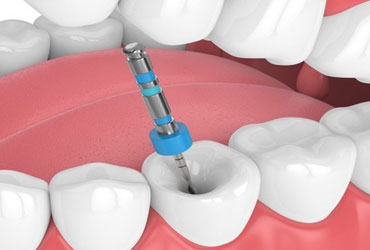

Root Canal

Root canal treatment is designed to eliminate bacteria from the infected root canal, prevent...